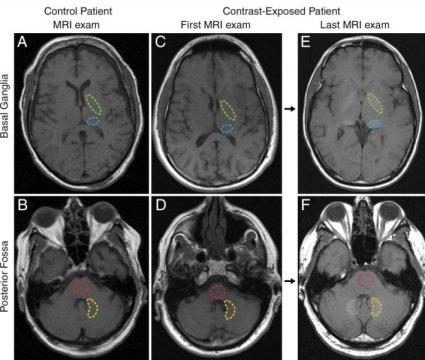

Le aree tratteggiate sono state controllate nei controlli (1a colonna), al primo esame RM (2a) e all'ultimo (3a), su due aree cerebrali. (Fonte: Radiological Society of North America)Non ci sono prove che l'accumulo nel cervello dell'elemento gadolinio acceleri il declino cognitivo, secondo un nuovo studio presentato oggi all'incontro annuale della Radiological Society of North America.

In precedenza gli scienziati ritenevano che il mezzo di contrasto gadolinio non riuscisse ad attraversare la barriera emato-encefalica, la membrana semipermeabile che filtra selettivamente i materiali dal flusso sanguigno che cercano di entrare nel fluido extracellulare nel cervello e nel sistema nervoso centrale. Tuttavia, studi recenti, compreso uno del Dr. McDonald e colleghi, hanno scoperto che tracce di gadolinio potrebbero restare per anni nel cervello dopo la risonanza magnetica.